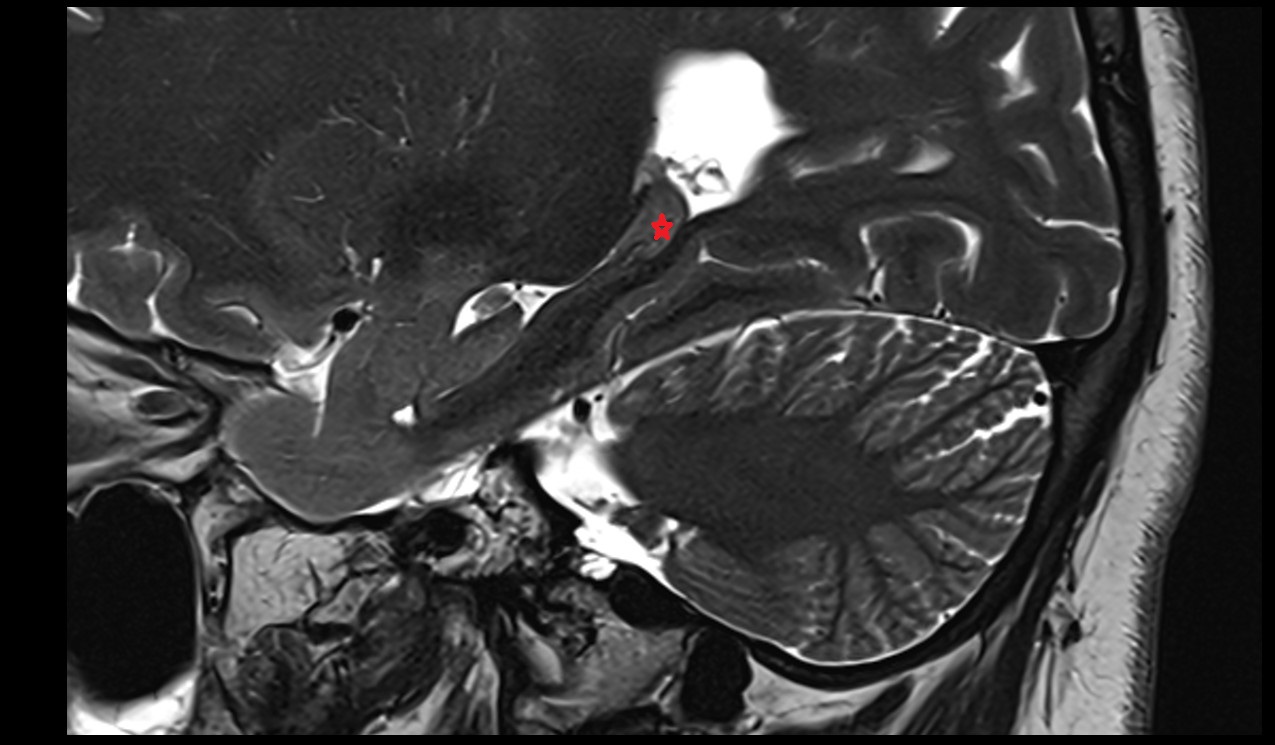

- Cerebral aqueduct

- Superior opening of cerebral aqueduct